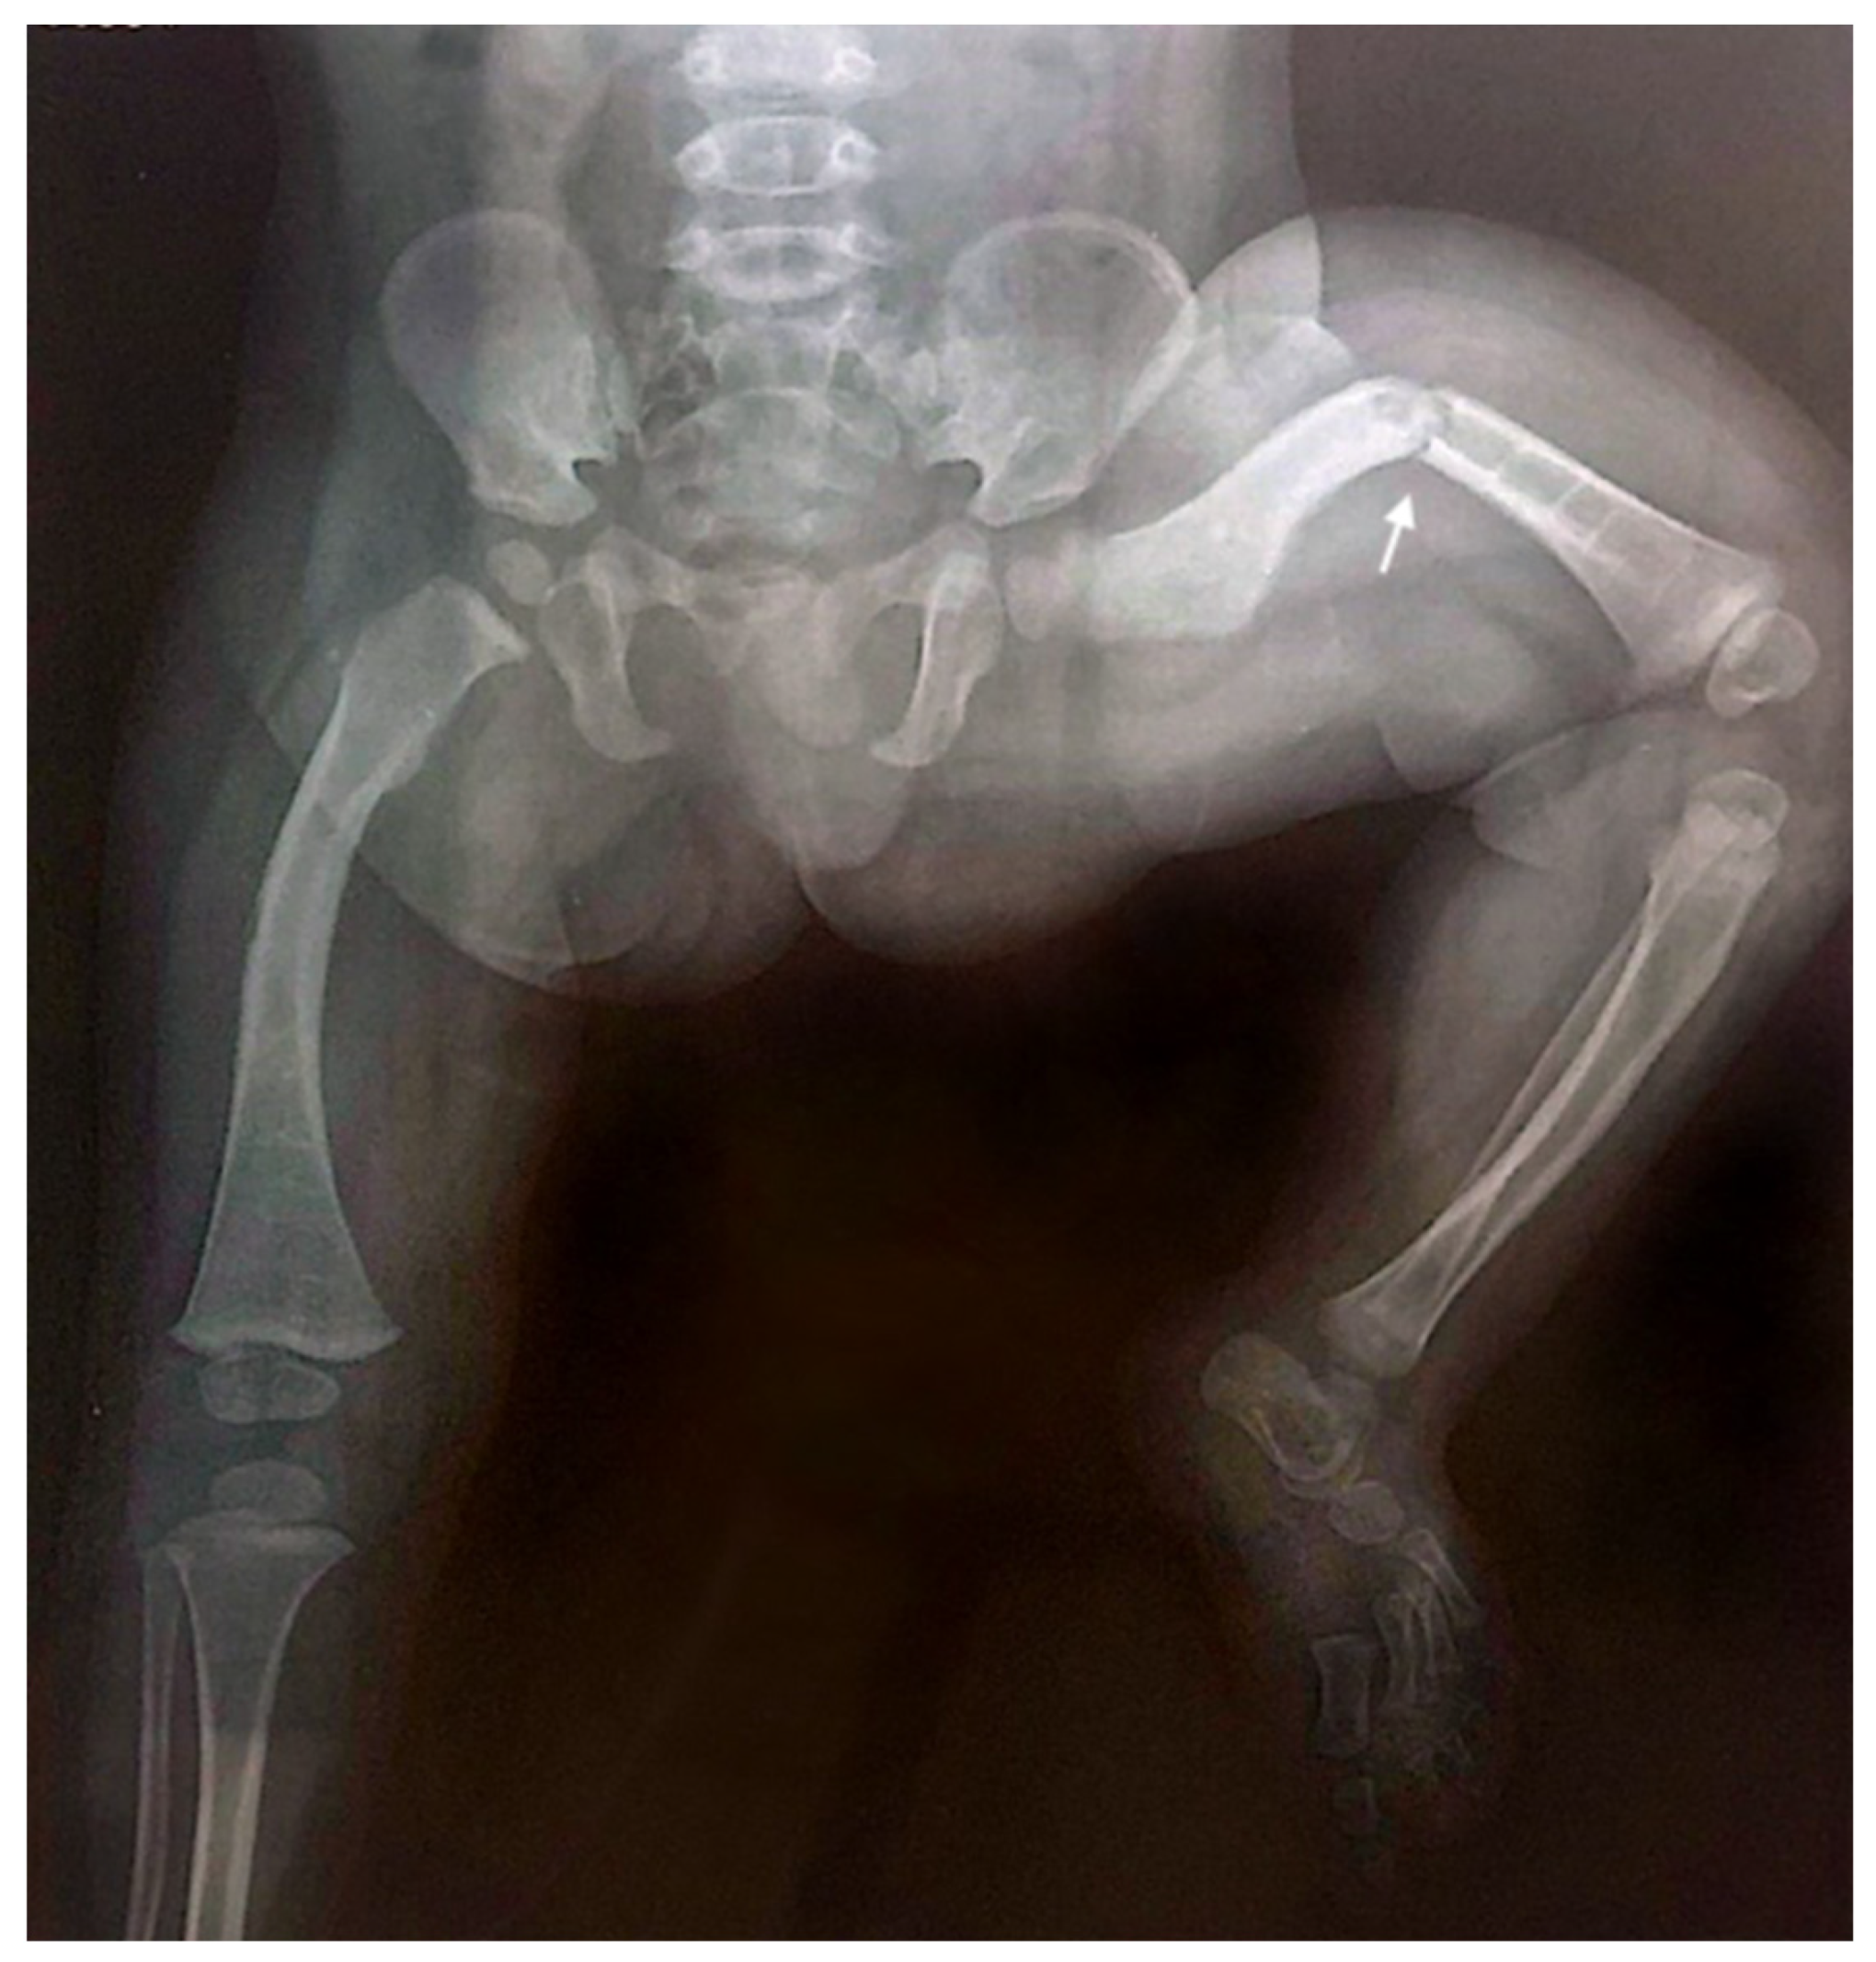

Throughout childhood and adolescence, the patient sustained eight fractures involving various skeletal sites, with four fractures affecting the left femur. The X-ray of the lower limbs taken at the age of one year and seven months demonstrated evidence of poor bone consolidation (Figure 3).

Figure 3. Anteroposterior radiograph of the lower limbs taken at the age of one year and seven months, showing poor consolidation of the left femoral fracture (indicated by the arrow), characterized by persistent displacement and inadequate callus formation. Generalized osteopenia is also observed, with diffusely reduced bone density consistent with the underlying condition.